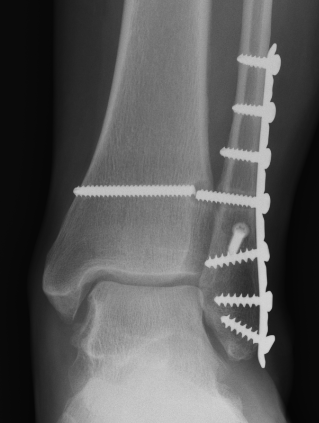

Isolated Weber C fracture

Weber C fracture Weber C fracture with deltoid ligament injury

Maisonneuve injury: proximal fibula with open medial clear space

Definition

Fracture above syndesmosis

Syndesmosis disrupted +/- deltoid ligament

Syndesmotic injury